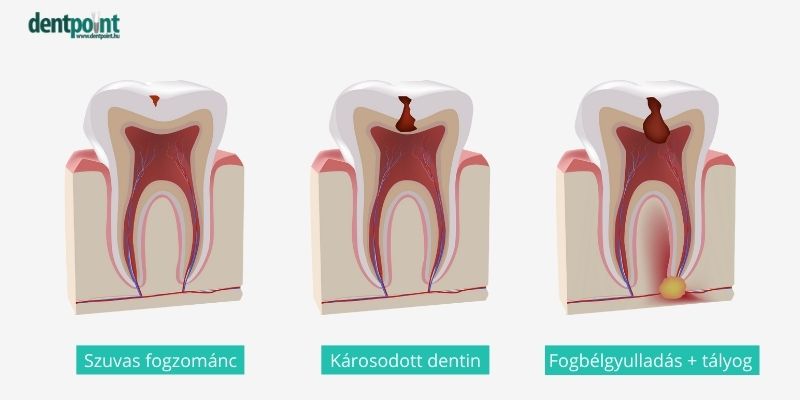

Fogbél gyulladásról akkor beszélünk, ha a fogbél (pulpa) gyullad be, amely a fog belső, idegekkel, erekkel átszőtt része. Kialakulhat a fogat ért trauma miatt vagy akkor, amikor egy kezeletlen fogszuvasodás már annyira mélyre hatol, hogy eléri a fog belső részét is. Köznyelvben ezt az állapotot szokták még foggyökér gyulladásnak is nevezni.

A fogszuvasodás kialakulása a fogakon képződő lepedéknek és a szájban található kórokozó baktériumoknak köszönhető.

Ha a baktériumok okozta savas kémhatás huzamosabb ideig fennáll, akkor a fog szerkezete irreverzibilisen sérül, köznyelven szólva a fog kilyukad. Lássuk, mi történik ezután!

- idegeket tartalmazó része között helyezkedik el, már hidegérzékenység, időszakos, vagy állandó fogfájás léphet fel.

- Ha a szuvasodást ekkor nem kezelik, és a dentin is átlyukad, akkor a fertőzés eléri a fogbelet, a fogbél begyullad, a fájdalom állandóvá és hevessé válik.

- Ha a páciens még ekkor sem látogat el a rendelőbe, akkor további szövődmények is kialakulhatnak, ezekről később külön írunk.

- A fogbélgyulladás hamar visszafordíthatatlanná válik, ilyenkor gyökérkezelésre van szükség vagy akár a fog eltávolítására is sor kerülhet.